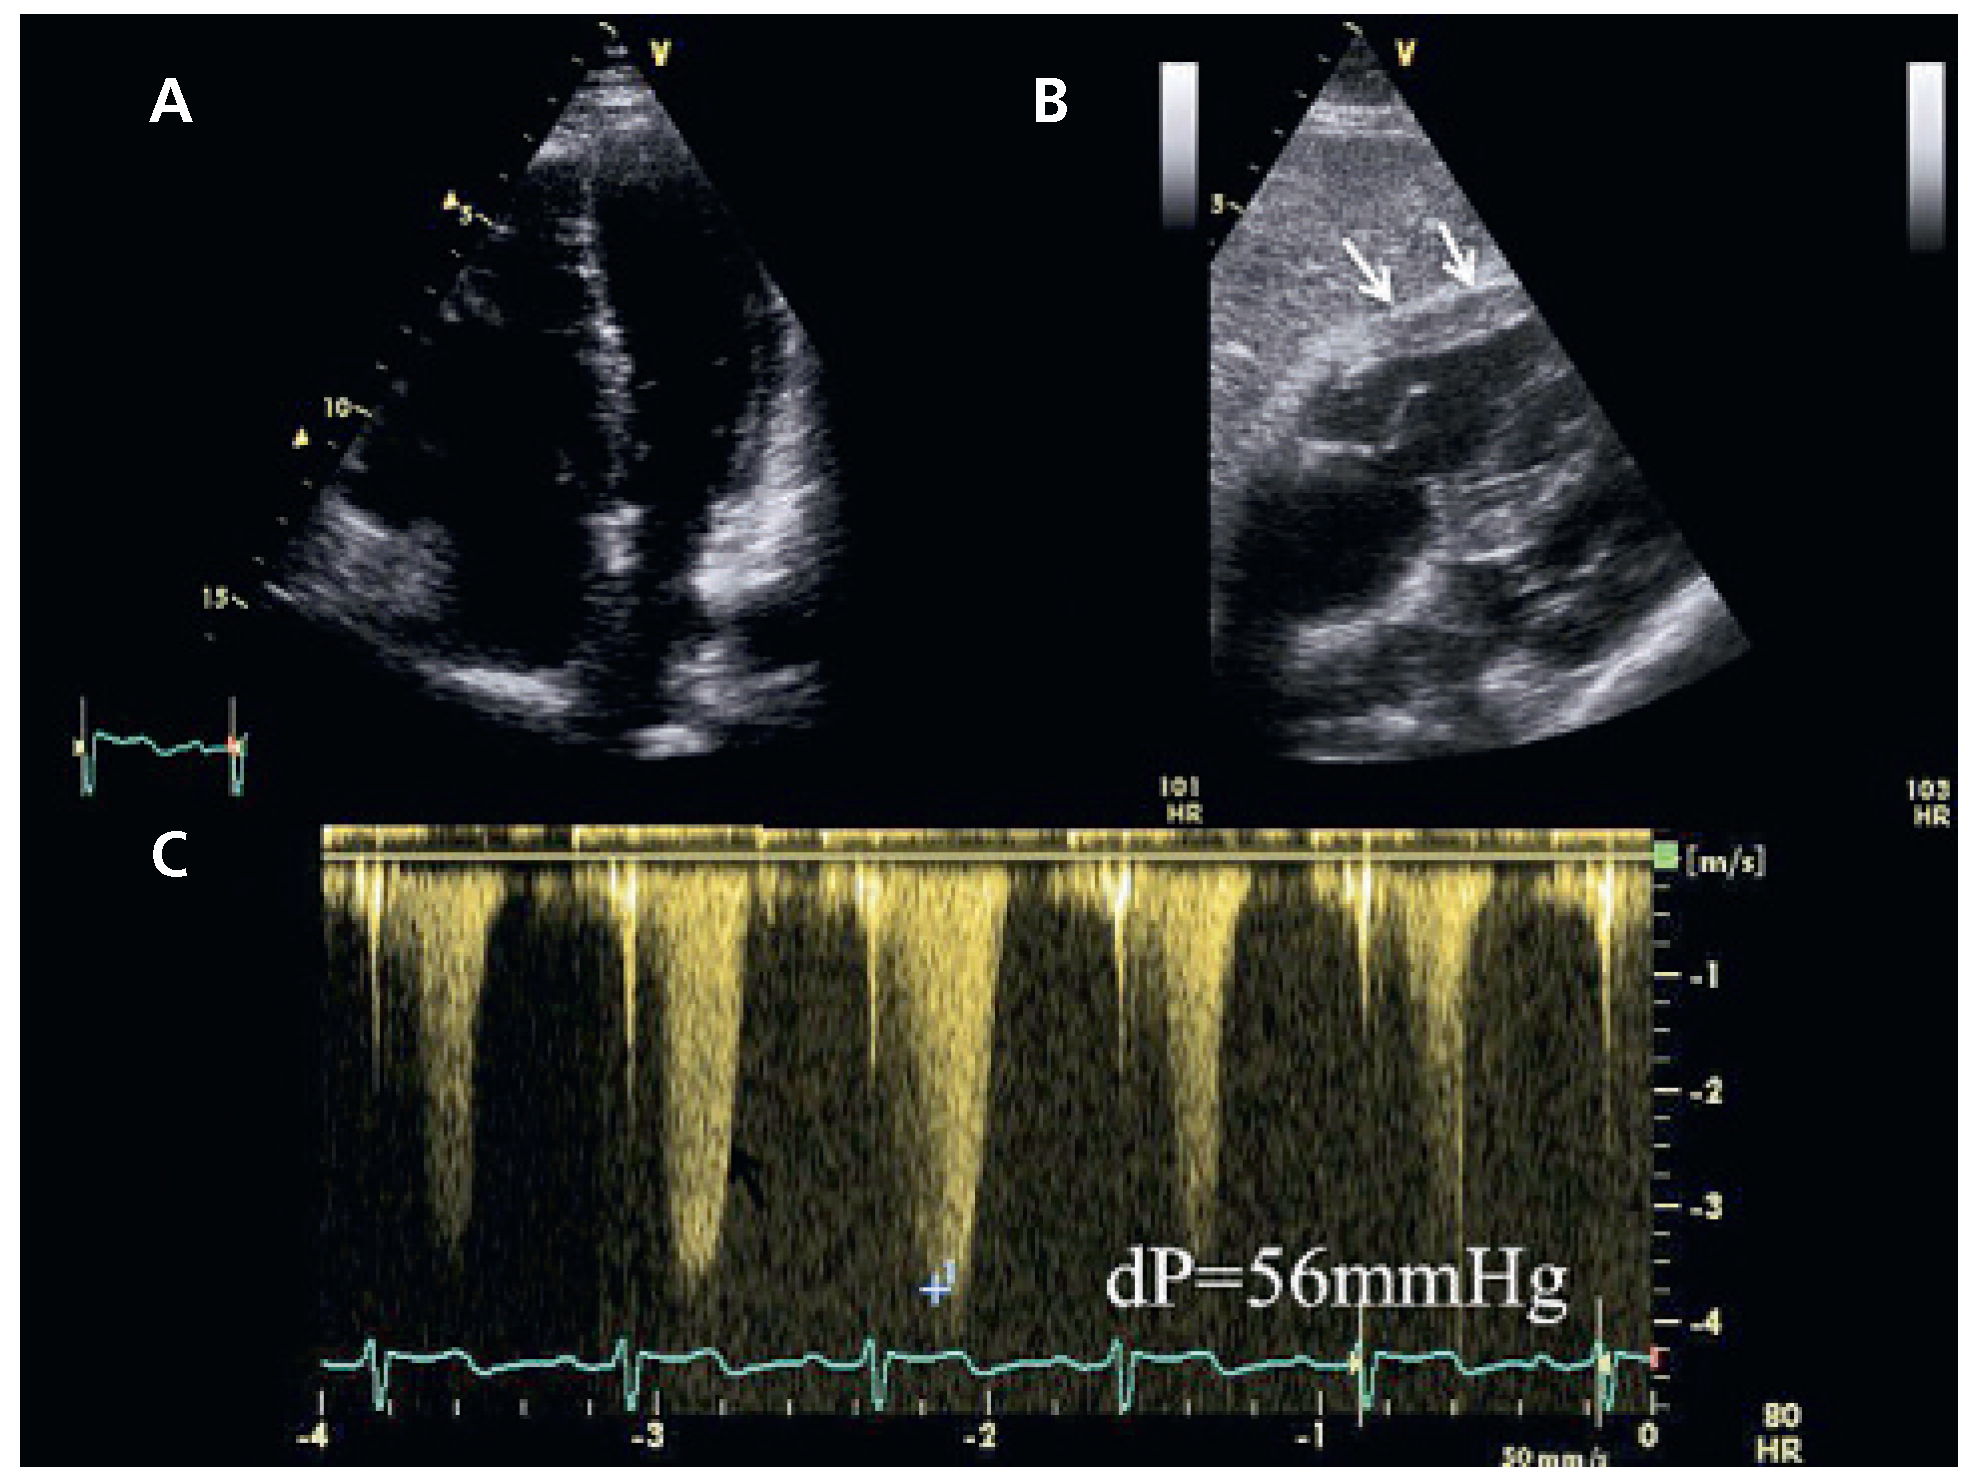

Un complément d’échocardiographie transthoracique est réalisé, permettant de visualiser le retour veineux anormal dans la veine innominée par une vue sus-sternale modifiée (Figure 3). A nouveau, un examen attentif du septum interauriculaire en apical 4 cavités et en sous-costal ne montre pas de communication inter-auriculaire (CIA) associée. Nous n’avons pas jugé utile de compléter les investigations par un examen trans-œsophagien en raison de l’état général précaire de la patiente et de l’absence de sanction thérapeutique.

Figure 3. A Vue sus-sternale modifiée montrant l’abouchement d’un vaisseau dans la veine innominée (flèches). B Le Doppler couleur confirme un drainage dans la veine innominée et non une veine cave supérieure gauche se drainant dans le sinus coronaire. C Flux continu au Doppler pulsé confirmant la nature veineuse du flux.